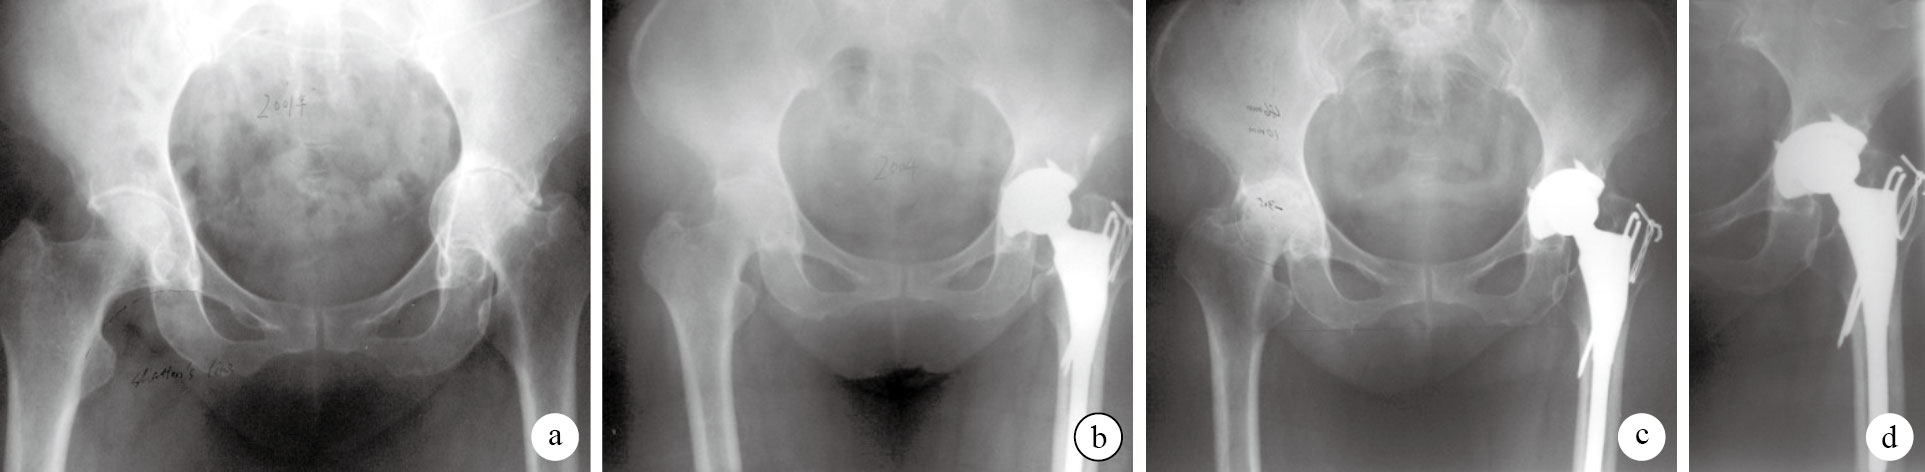

本組手術時間48~126 min,平均74 min;失血量150~650 mL,平均350 mL。術后2例切口愈合不良,經換藥后愈合;其余患者切口均Ⅰ期愈合。無假體周圍感染發生。3例出現下肢深靜脈血栓形成,給予低分子肝素治療3個月,無肺栓塞發生。患者均獲隨訪,隨訪時間60~156個月,平均108個月。X線片示術后6個月內自體移植骨均與髖臼融合。末次隨訪時髖臼內陷(-1.11±0.45)mm,與術前比較差異有統計學意義(t=5.66,P=0.00);Harris評分為(87.20±4.21)分,與術前比較差異有統計學意義(t=-27.68,P=0.00)。結合X線片以及臨床表現,本組隨訪期間均無髖臼假體松動發生。見圖 1。